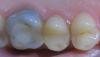

Дата первых двух фотографий - 26.02.2010, дата снимка на третьей - 19.08.2008

Нарыв образовался в сентябре 2007го после неаккуратного обращения с зубной щёткой (ударила пластиковым корпусом) и до сих пор живёт своей жизнью. Регулярно то увеличивается, то уменьшается. Когда слишком много гноя, придавливаю - выходит. Всякие мази и примочки - пройденный этап, бесполезно. По снимку врач сказала, что это свич(прямо из корня), и что всё само пройдёт, когда раскрыть зуб и несколько дней пролечить изнутри. Продолжить лечение не получилось из-за работы, а дальше просто затянула, натура такая нехорошая всё делать в последний момент...

Зубная щетка не имеет отношения к образованию свища. И само не пройдет, а пройдет, если хороший профессионал хорошенько потрудится, зуб не самый простой. И если все получится, то закрепите успех восстановив зуб культевой вкладкой и коронкой.